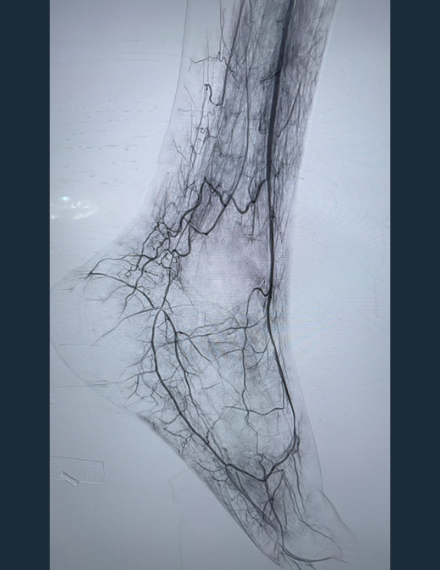

Final Angio

Brisk flow restored throughout treated vasculature